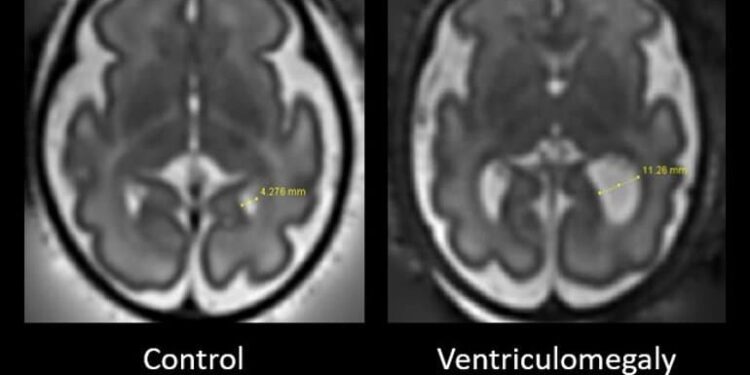

Fetal ventriculomegaly is the most common antenatally-diagnosed brain abnormality and is diagnosed when the lateral ventricles measure larger than normal on antenatal ultrasound or MR imaging.

Fetal ventriculomegaly is the most common antenatally-diagnosed brain abnormality. Imaging studies in antenatal isolated ventriculomegaly demonstrate enlarged ventricles and cortical overgrowth which are also present in children with autism-spectrum disorder/condition (ASD).

We investigate the presence of ASD traits in a cohort of children (n = 24 [20 males/4 females]) with isolated fetal ventriculomegaly, compared with 10 controls (n = 10 [6 males/4 females]).